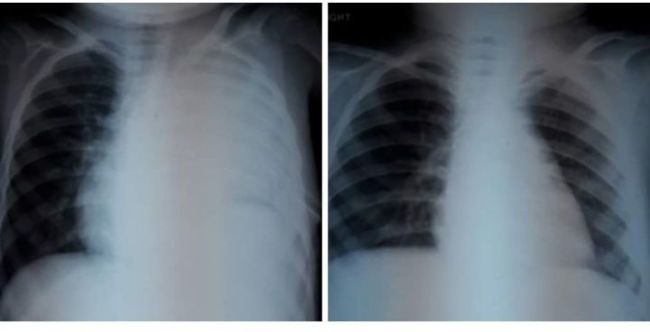

IGIMS पटना में कैंसर पीड़ित बच्चे की जान बचाकर अस्पताल के कैंसर विभाग ने एक बार फिर मिसाल कायम की है. मौत की दहलीज पर पहुंच चुके एक गरीब परिवार के बच्चे का ना सिर्फ इलाज किया बल्कि उसे नई जिंदगी दी है. IGIMS के कैंसर विभाग के हेड डॉ अविनाश पांडे ने बताया कि एक 5 साल के बच्चे को सांस लेने में तकलीफ और फीवर की शिकायत थी. एक्स रे के बाद गांव में उसका गलत इलाज किया गया और करीब 3 हफ्ते तक टीबी और टायफायड की दवा चलाई गई.

एक हफ्ते में ही बच्चे की हालत में तेजी से सुधार हुआ और करीब एक महीेने की इंटेसिव थेरेपी के बाद अब उसे नॉर्मल एक्स रे और स्वास्थ्य के साथ अस्पताल से छुट्टी मिल गई.